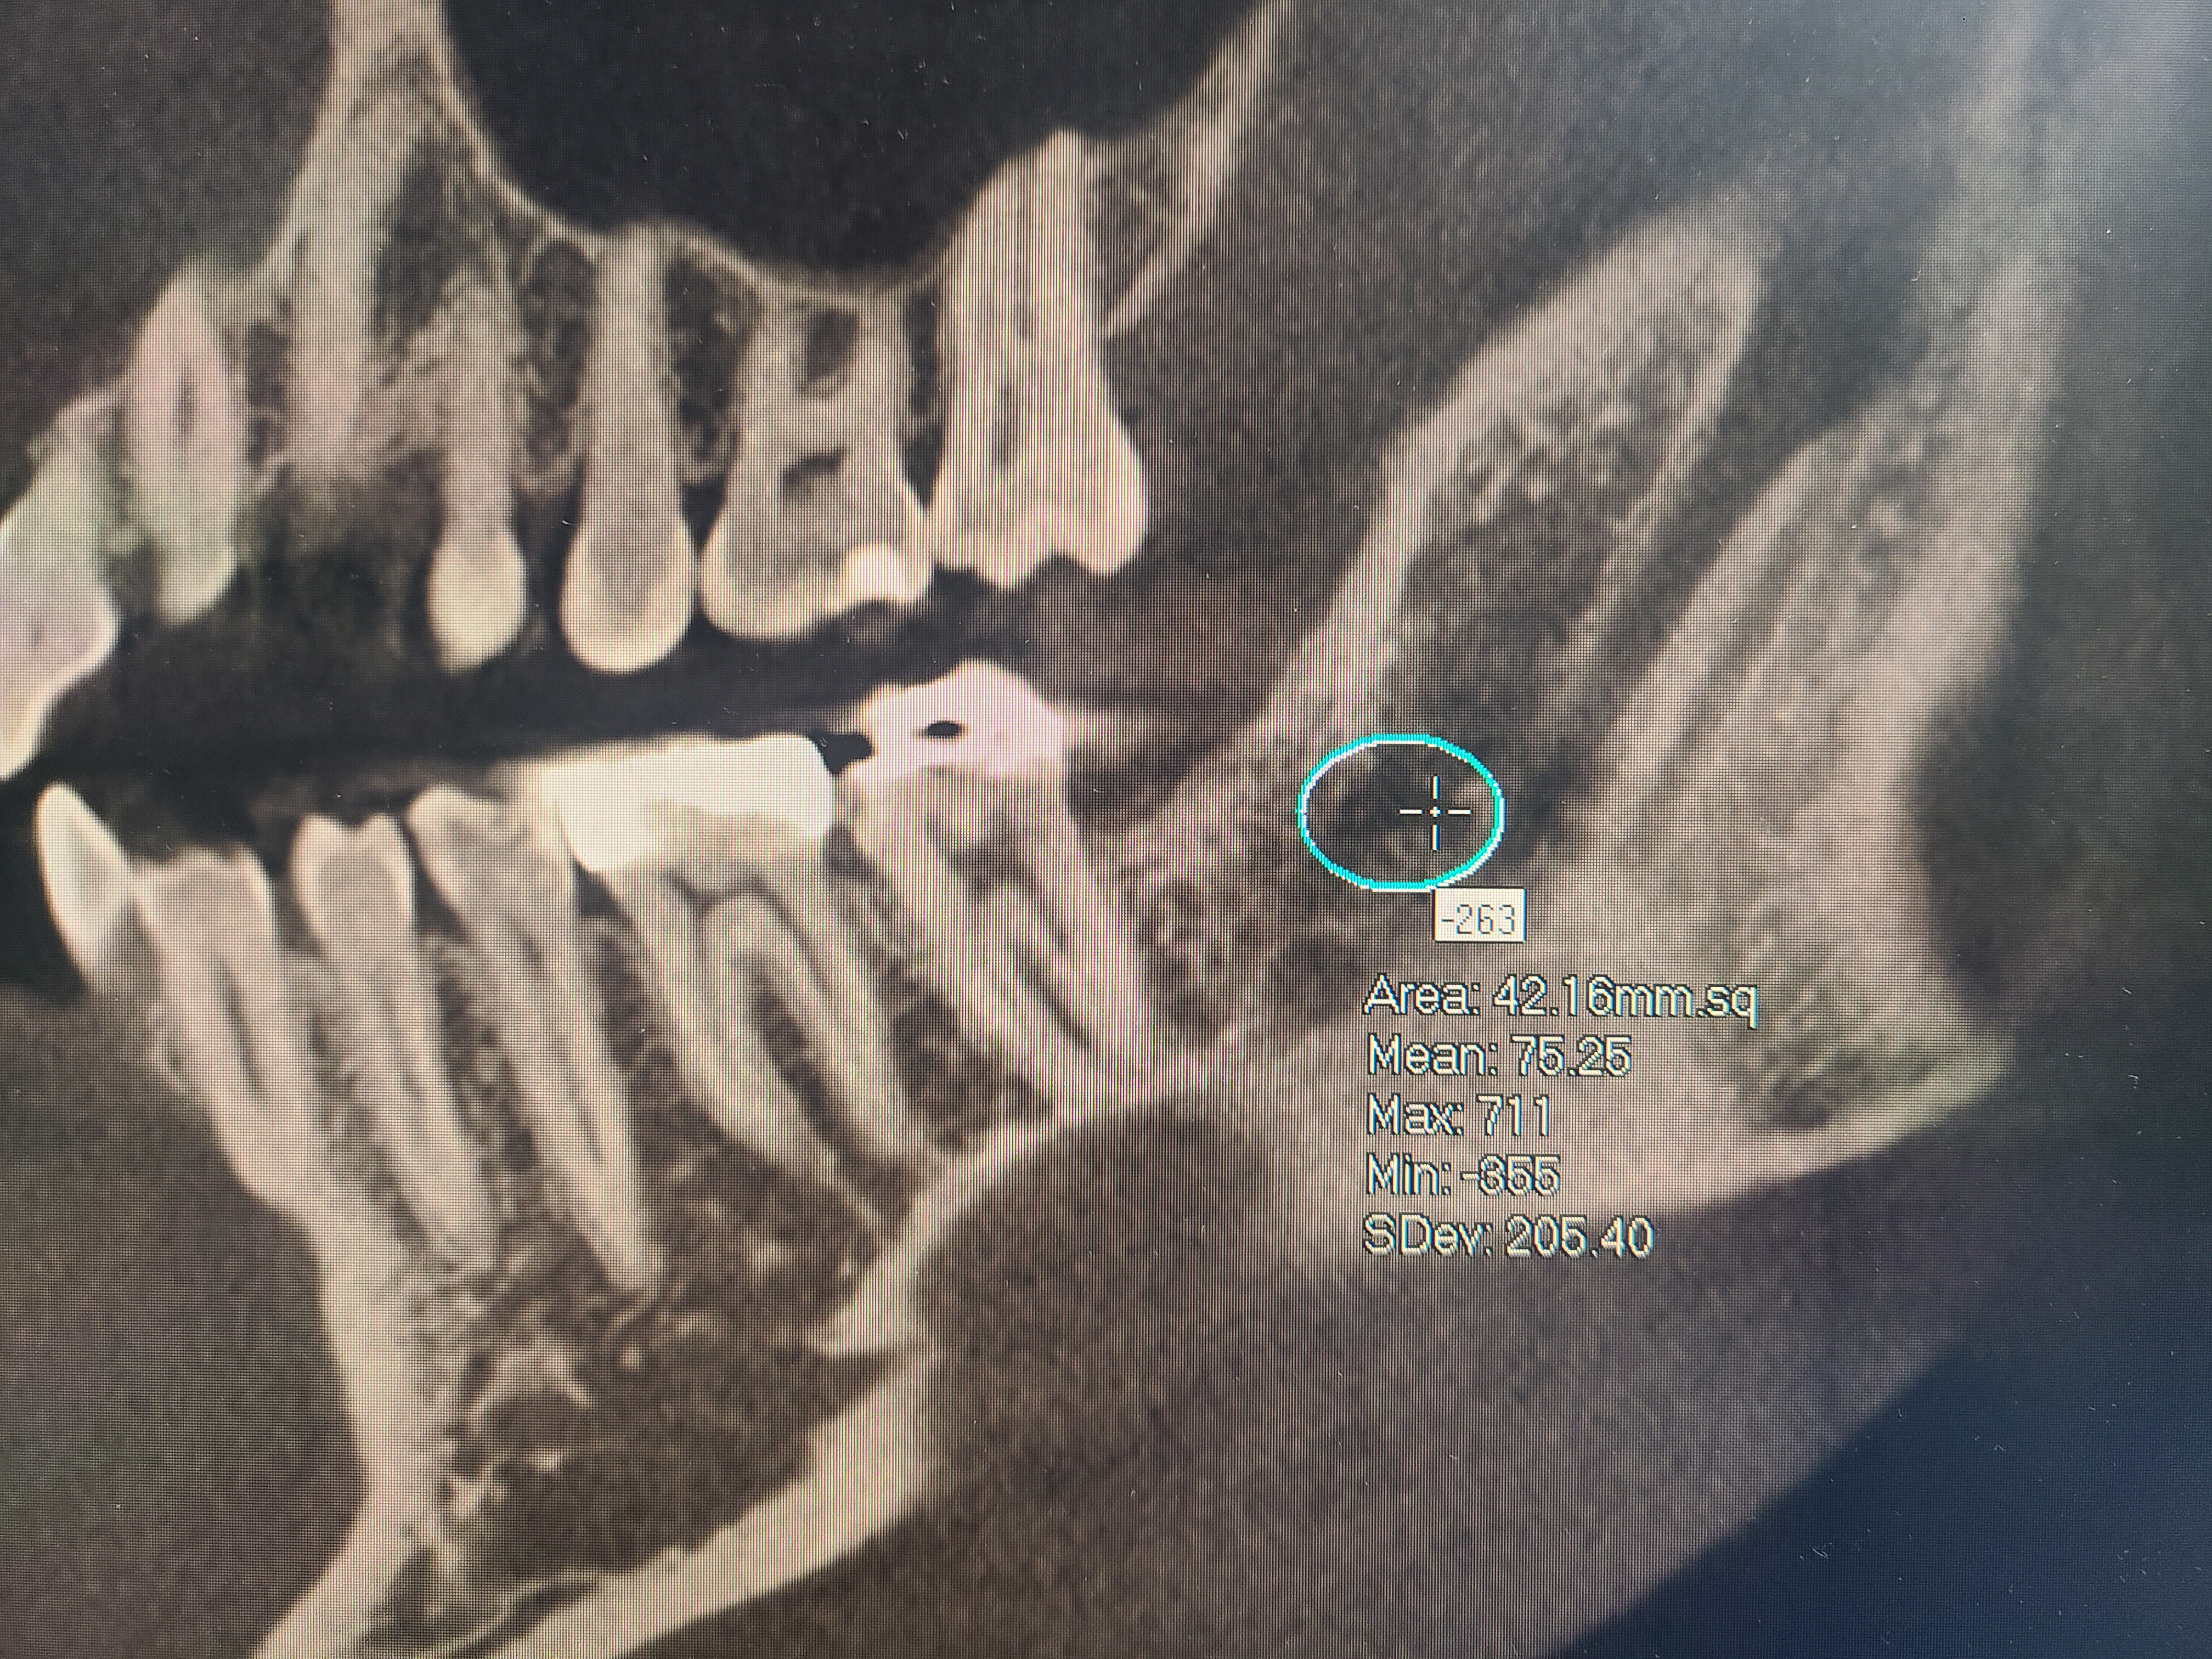

Bone cavitations could be tricky to diagnose, a simple x-ray or panoramic x-ray will not be enough. The best way to diagnose a bone cavitation is with a CT Scan or Cone Beam CT. There are specific CT Scans that can measure bone density. Bone density should not have a negative number. Readings of a (-100) or more are indicators of bone cavitation. They are usually located at extraction sites. For more information, do not hesitate to schedule a consultation with us. We would be honored to have you.